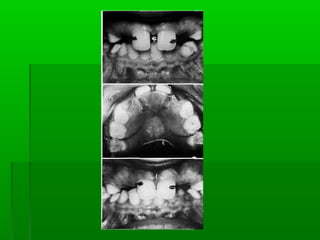

 Radiographic examinationRadiographic examination

to check the no. of teethto check the no. of teeth

to detect the intrabony lesionto detect the intrabony lesion

to assess the frenum attachmentto assess the frenum attachment

radiographically, there is a V shaped notch in theradiographically, there is a V shaped notch in the

interdental bone between 1 1 indicating theinterdental bone between 1 1 indicating the

attachment of frenum.attachment of frenum.

 Radiographic examinationRadiographicexamination to check the no. of teethto check the no. of teeth to detect the intrabony lesionto detect the intrabony lesion to assess the frenum attachmentto assess the frenum attachment radiographically, there is a V shaped notch in theradiographically, there is a V shaped notch in the interdental bone between 1 1 indicating theinterdental bone between 1 1 indicating the attachment of frenum.attachment of frenum.